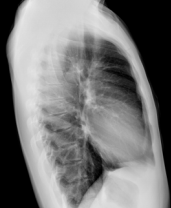

▪ Intelligent Algorithm for High-Resolution Image

▪ Image processing: Image enhancement, balance, noise reduction

▪ The image gray scale can be adjusted automatically or manually

▪ The specific screening program for pneumoconiosis

Intelligent Algorithm for High Resolution Image

▪ Image processing: Image enhancement, balance, noise reduction

▪ Image gray scale can be adjuste dautomatically or manually

▪ Specific screening program for pneumoconiosis

| C-spine | Chest | Chest |